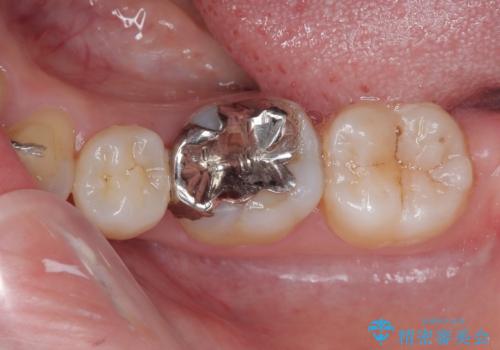

- 左下の銀歯のところがしみるとのことで来院された患者様です。

レントゲン上で金属の詰め物(メタルインレー)の下に虫歯を認めました。

拡大鏡視野下で、金属の詰め物(メタルインレー)、虫歯の除去を行い、オールセラミッククラウンに適した形に整えました。